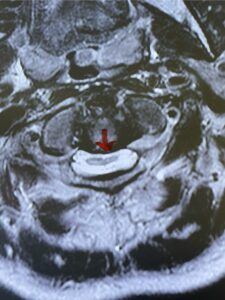

This is a 59 year-old female with a history of cerebral palsy and a prior C3-C7 posterior cervical laminectomy and instrumented fusion two years prior. She did ok until she developed progressive weakness of all four extremities and numbness. Imaging revealed she had a significant breakdown above the fusion at C2-3 with a grade 2-3 spondylolisthesis of C2 on C3 with severe spinal cord compression (Fig. 9). It was surprising the degree of anterior fusion induced by the posterior fusion from C 3-C 7 (Fig. 10). Because of her progressive neurological dysfunction in a patient who was already compromised because of her cerebral palsy, it was clearly necessary to decompress from occiput to C 3. We utilized her prior lateral mass screws although we removed bilaterally the C7 screws to reduce the fulcrum-effect on the C7-T1 junction as the C 6-7 level was solidly fused. We performed an occiput to C 6 fusion with occiput to C3 laminectomy (Fig. 11) Post operatively we had good placement and alignment (Fig. 12) The patient went to rehab with improvement of strength and numbness particularly in hands.

Fig. 9: Sagittal T2-weighted cervical MRI demonstrating severe upper cervical spinal cord compression secondary to C2 anterior subluxation on C3 with development of thickened posterior degenerative material (red arrow).

Fig. 10: Sagittal cervical CT scan demonstrating grade 2-3 subluxation of C2 on C3 above prior C3 to C7 posterior instrumented fusion and laminectomy (red arrow). Note the unusual significant anterior auto fusion resulting from prior posterior construct (red dot).